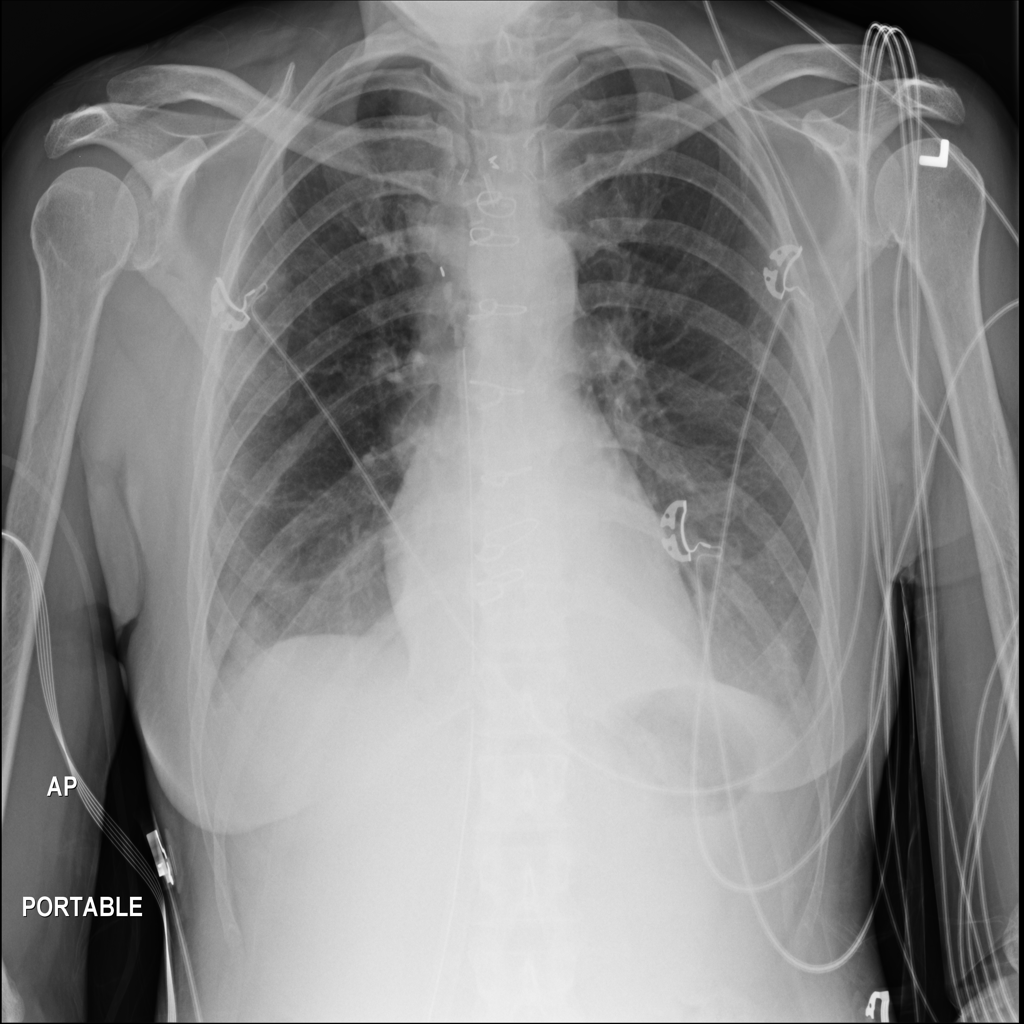

PAT-4639 · IMG-012Pneumothorax

PAT-4639 · IMG-012

AP